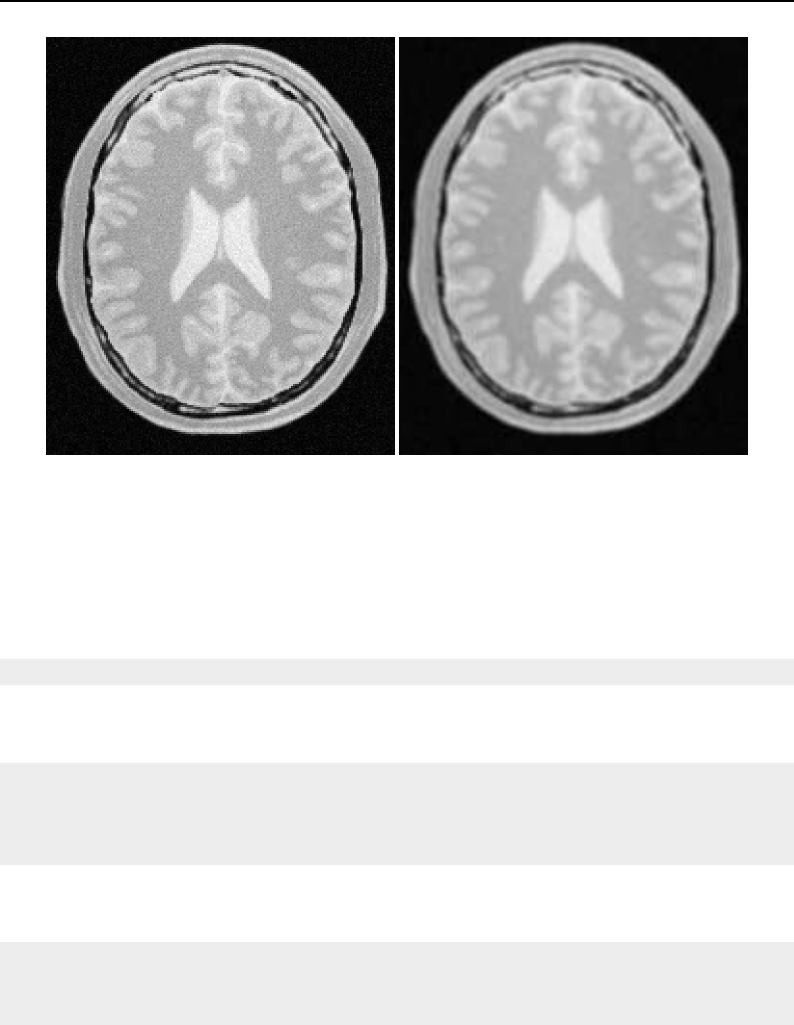

The National Library of Medicine Insight Segmentation and Registration Toolkit, shortened as the

Insight Toolkit (ITK), is an open-source software toolkit for performing registration and segmenta-

tion. Segmentation is the process of identifying and classifying data found in a digitally sampled

representation. Typically the sampled representation is an image acquired from such medical instru-

mentation as CT or MRI scanners. Registration is the task of aligning or developing correspondences

between data. For example, in the medical environment, a CT scan may be aligned with a MRI scan

in order to combine the information contained in both.